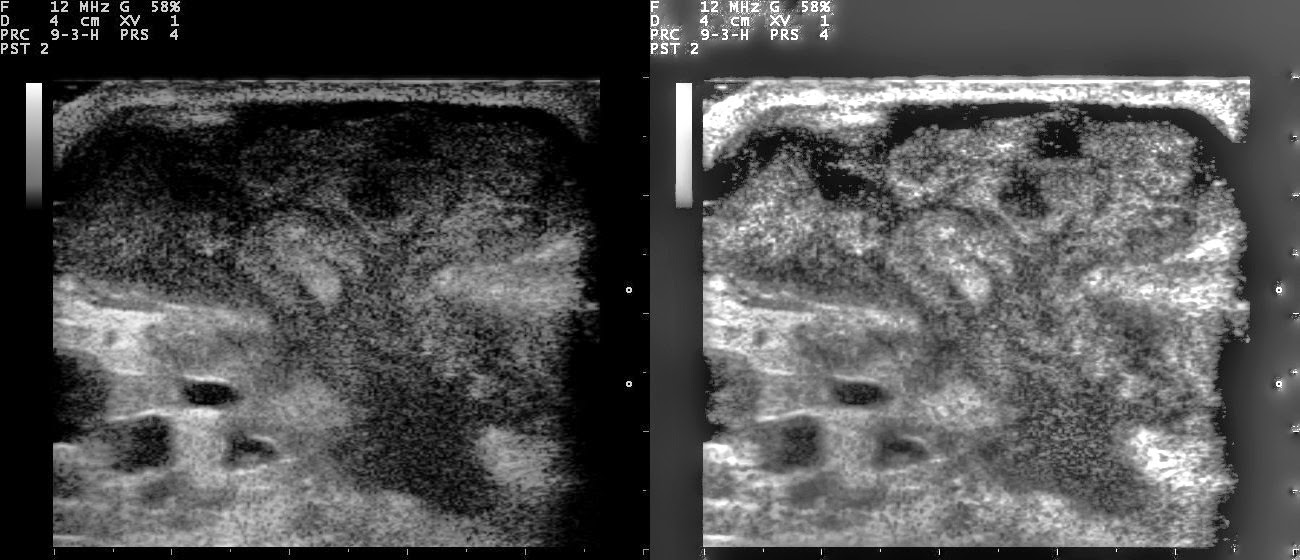

El ultrasonido mamario es una herramienta vital en la detección y evaluación de afecciones mamarias, pero ¿necesitas una remisión médica para acceder a este examen? En este artículo, abordaremos esta pregunta común y proporcionaremos información relevante sobre cómo acceder a un ultrasonido mamario.

Cabe destacar que algunos centros de diagnóstico por imagen ofrecen servicios de imagen directa al paciente, lo que significa que puedes programar un ultrasonido mamario por tu cuenta sin una remisión médica previa. Estos centros pueden ofrecer citas flexibles y acceso rápido a los resultados del examen, lo que puede ser especialmente útil si estás preocupado por los cambios en tus senos o si deseas una evaluación adicional de tu salud mamaria.

La salud mamaria es una parte importante del bienestar general de la mujer. Si estás preocupado por los cambios en tus senos o si tienes antecedentes familiares de enfermedades mamarias, te recomendamos que hables con tu médico sobre la posibilidad de someterte a un ultrasonido mamario. Estos exámenes pueden ayudar a detectar problemas en etapas tempranas, cuando son más tratables, y brindarte tranquilidad sobre tu salud mamaria. No dudes en tomar medidas proactivas para cuidar de ti mismo y programar una prueba de ultrasonido mamario si lo consideras necesario. Tu salud es valiosa y merece toda tu atención y cuidado.